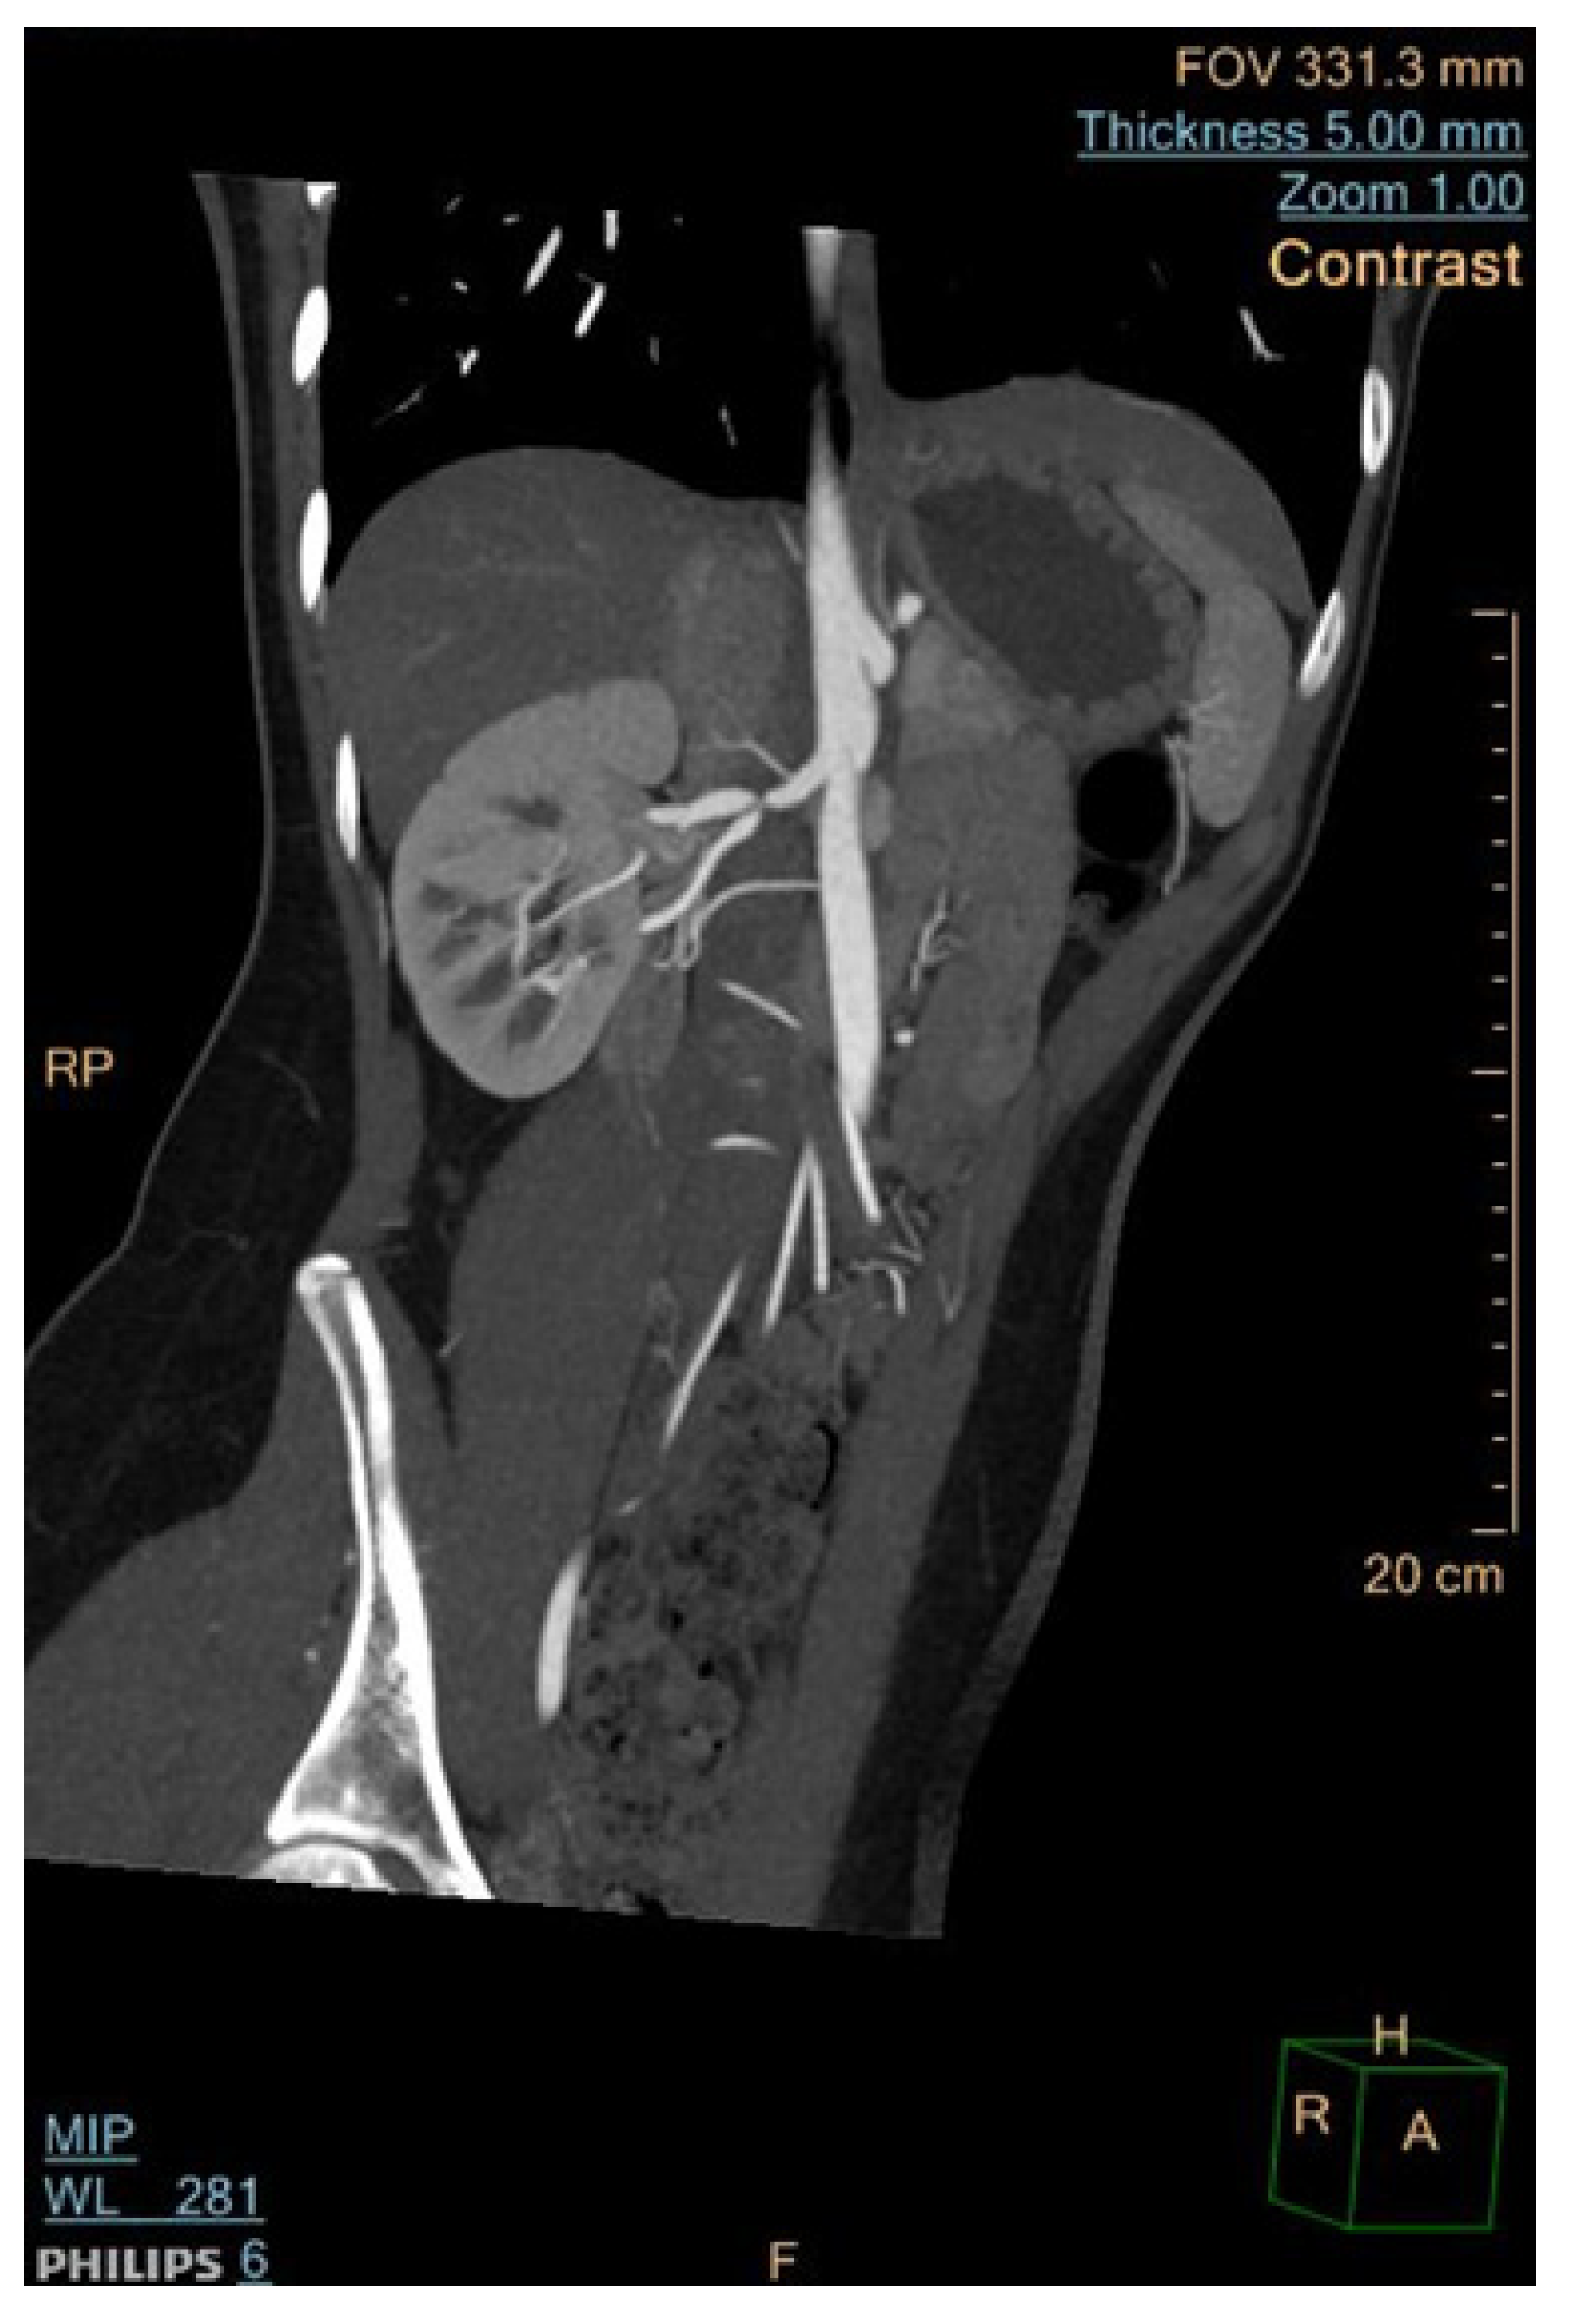

6.2. Computed Tomographic Angiography (CTA)

- Cai, Z.; Bai, E.-W.; Wang, G. A Reduced Radiation Dose CTA. IFAC Proc. Vol. 2012, 45, 184–189. [Google Scholar] [CrossRef]

- Roebuck, D.J. Childhood hypertension: What does the radiologist contribute? Pediatr. Radiol. 2008, 38, 501–507. [Google Scholar] [CrossRef] [PubMed]

3.4. Mid-Aortic Syndrome